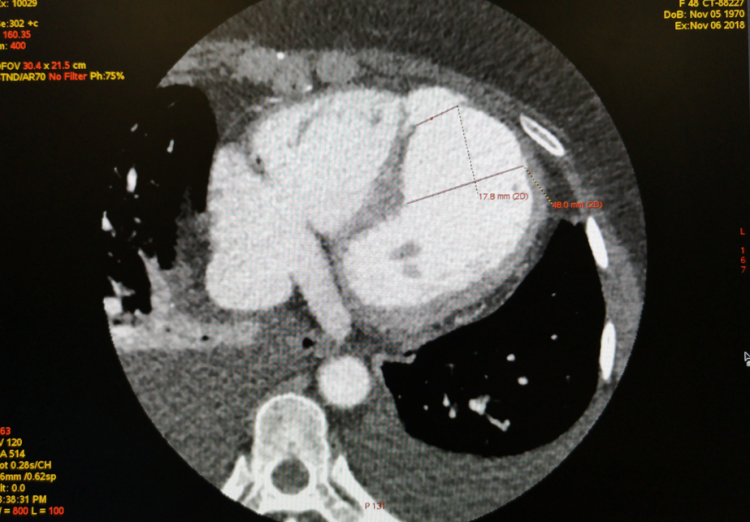

首例会诊患者因“急诊PCI术后冠脉急性闭塞、室壁瘤形成、室间隔穿孔”于11月5日从外院转入我院治疗,住院第二天即心衰症状加重急行IABP植入术。患者各项指标经治疗后逐渐好转,但检查发现其再发心梗、室间隔穿孔明显扩大。考虑到患者病情较为复杂,手术存在较大风险,为保障患者安全和医疗质量,经医院内病例讨论决定紧急邀请阜外医院专家提供技术支持,并顺利在我院ICU连线完成远程多学科疑难病例会诊讨论。